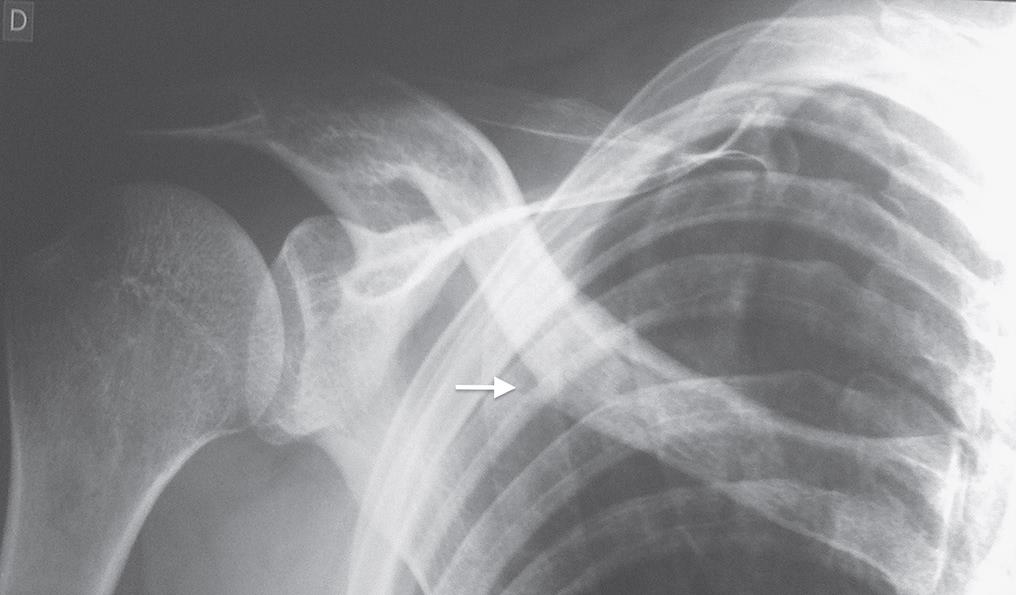

Como é feito o diagnóstico da fratura traumática de arcos-costais?

Para que o diagnóstico seja feito da forma correta, é importante que o profissional utilize uma combinação de história clínica, exame físico e exames de imagens, a fim de confirmar a lesão.